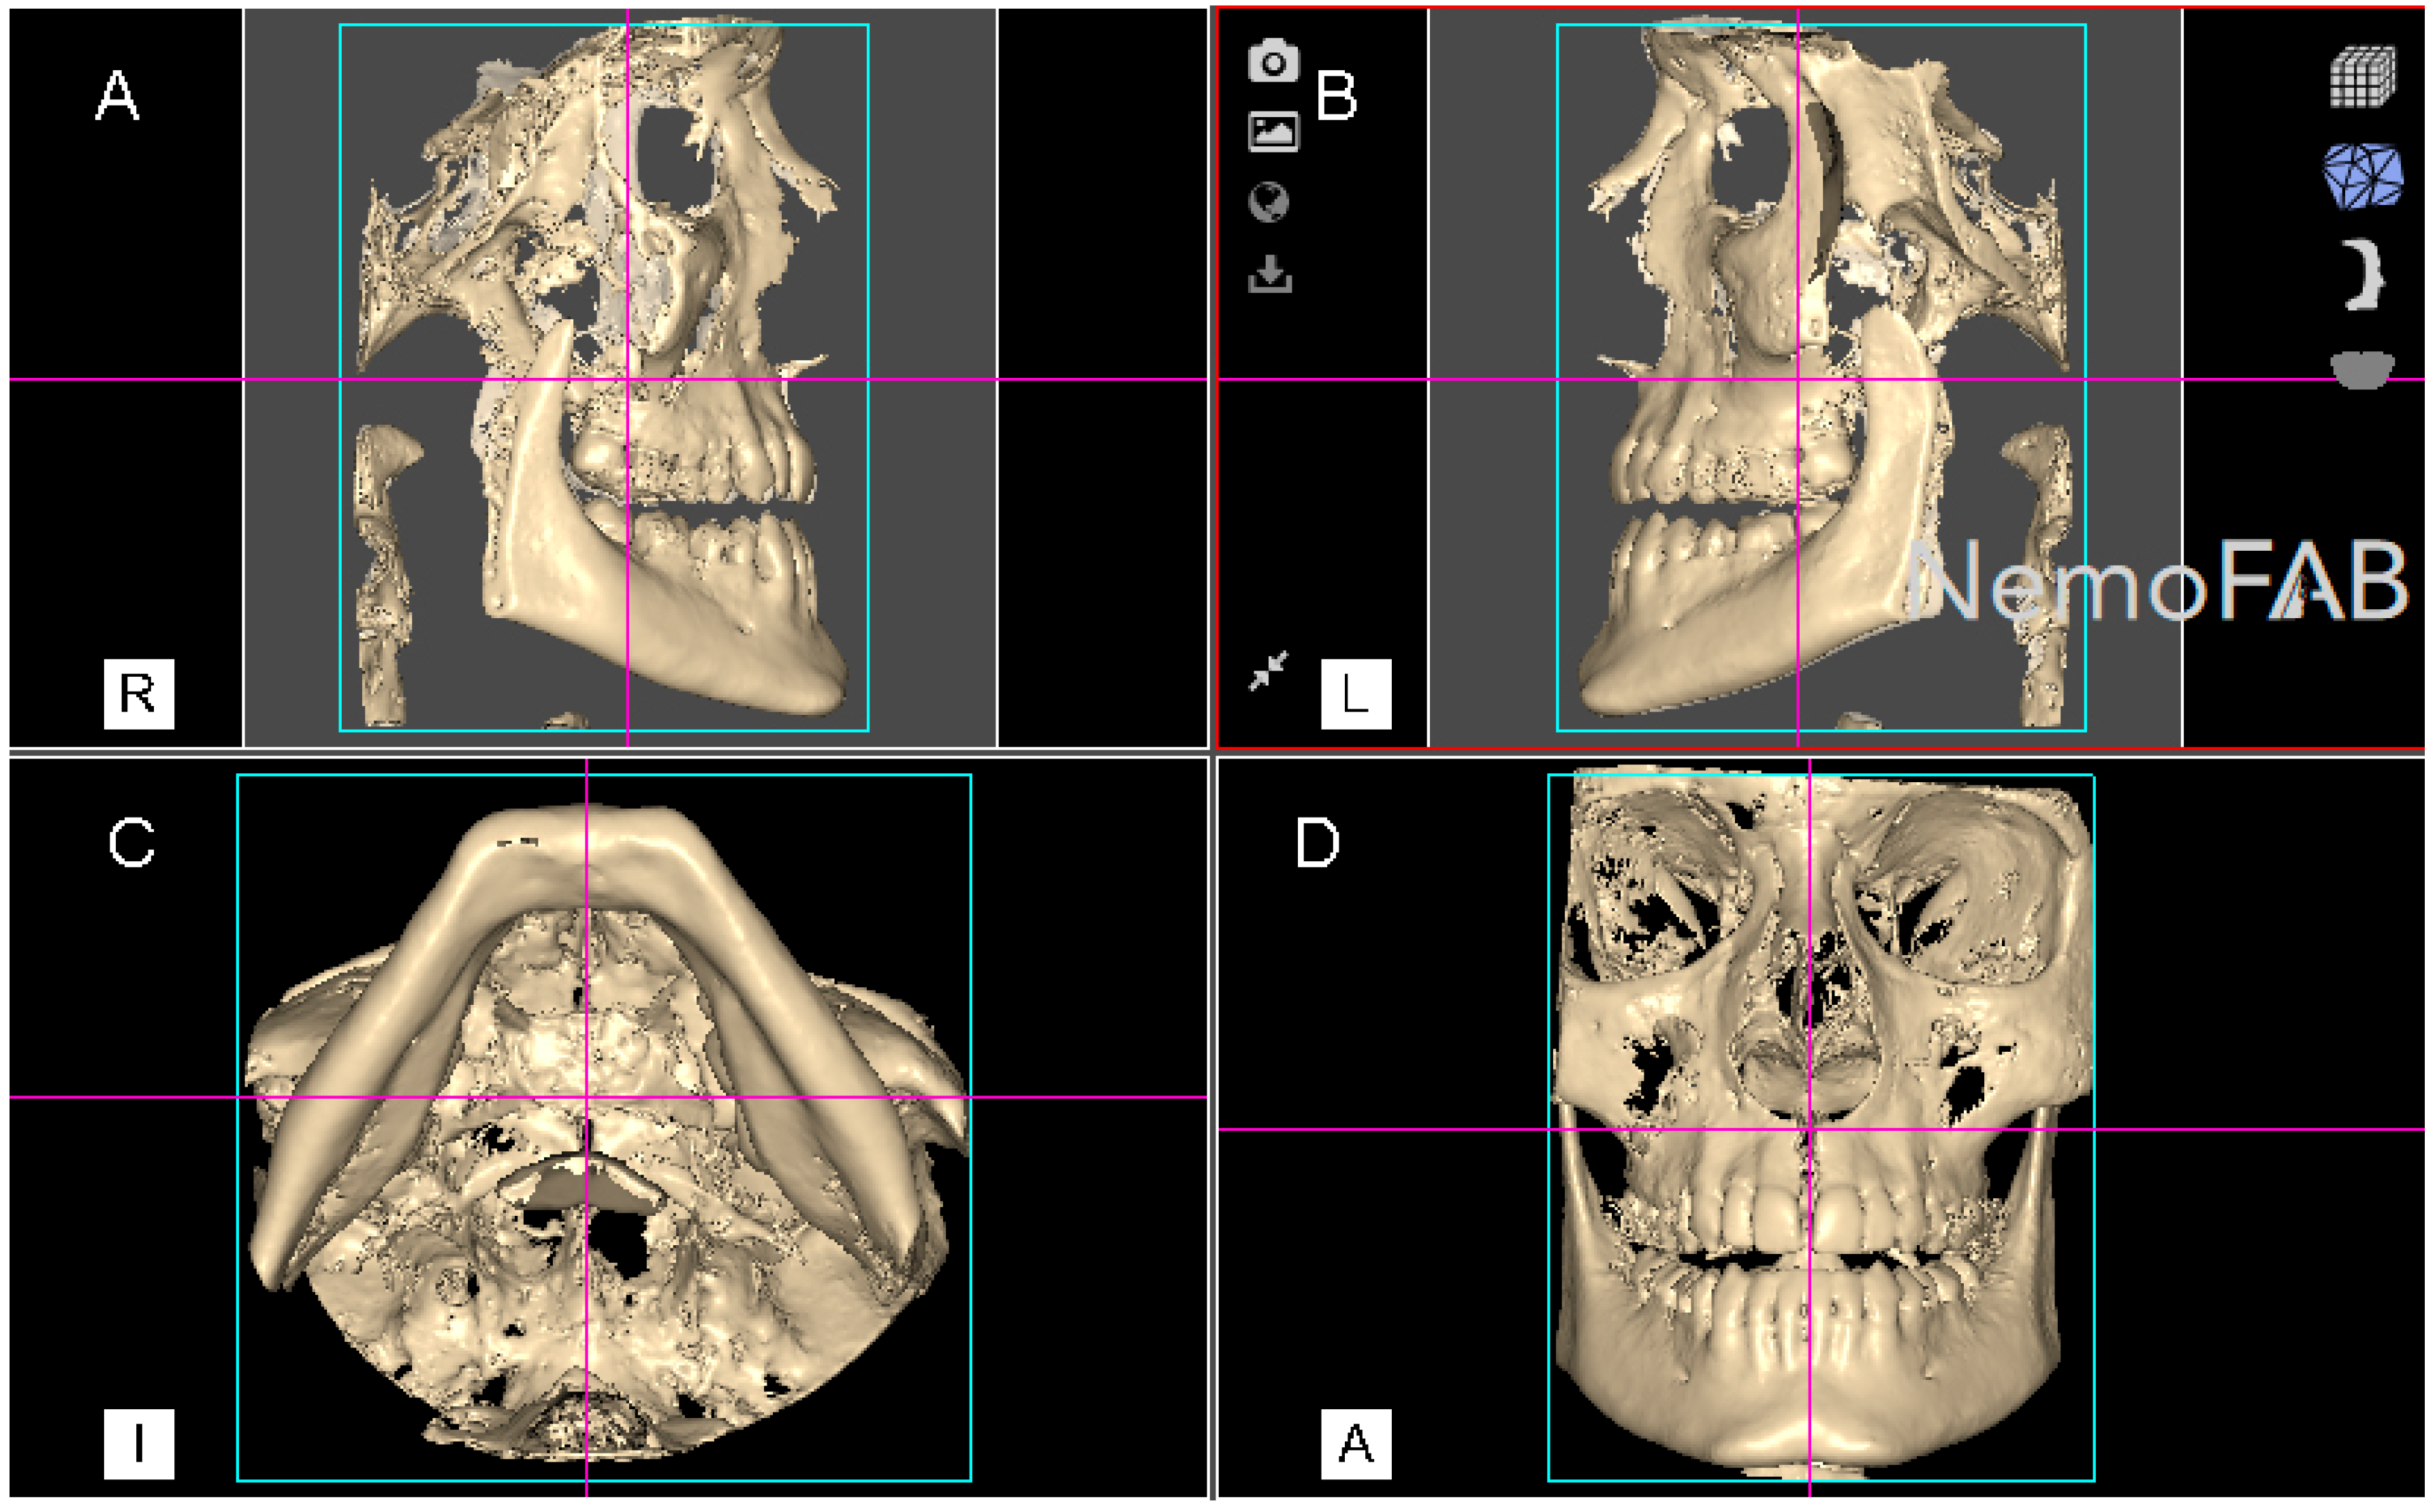

Then, the geometric prism of the expanded palatine suture was selected and isolated by analyzing the boundaries of the palatine suture expansion in transversal (Figure 3A), sagittal (Figure 3B), coronal (Figure 3C) plane and the three-dimensional reconstruction of the CBCT scan (WhiteFox, Satelec, Merignac, France) (Figure 3D). Subsequently, the anatomical references that delimited the boundaries of the geometric prism after the palatine suture expansion were identified by the two anterior nasal spines and the two posterior nasal spines.

Figure 3.

(A) Boundaries of the palatine suture (blue line) after the RME procedure through McNamara appliance was performed, at transversal plane, (B) sagittal plane, (C) coronal plane and (D) at three-dimensional reconstruction of the CBCT scan.